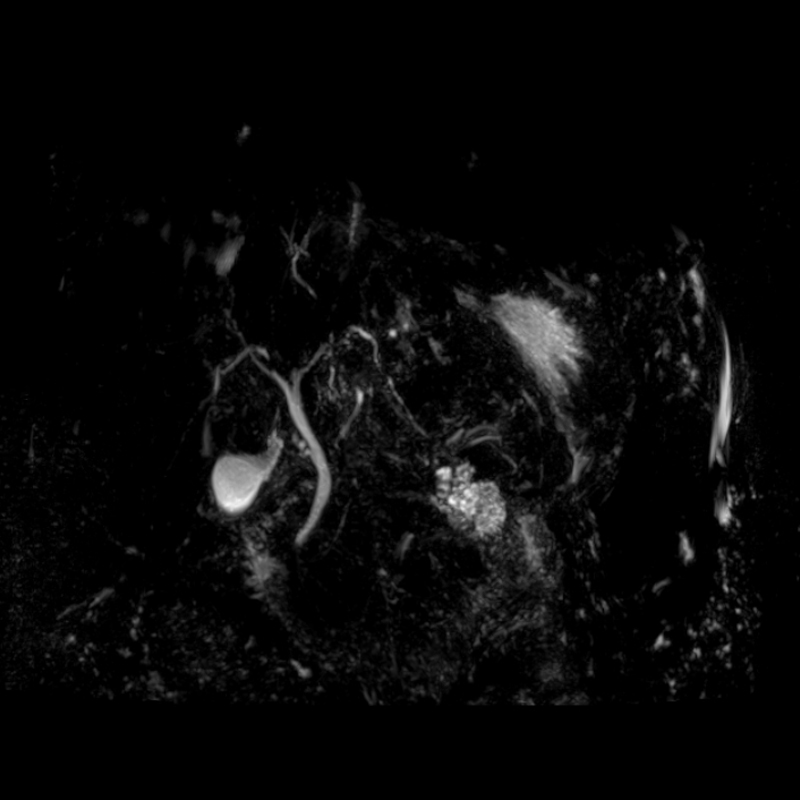

Kontrast Kullanımına Alternatif:

Bazı incelemelerde kontrast madde kullanımı gerekliliği azalabilir, çünkü doğal kontrastlar daha belirgin hale gelir.

4. Kontrast Kullanımına Alternatif:

o Bazı incelemelerde kontrast madde kullanımı gerekliliği azalabilir, çünkü doğal kontrastlar daha belirgin hale gelir.

Beyin fonksiyonlarını (fMRI), doku metabolizmasını (MR spektroskopi) ve kan akışını değerlendirmek için uygundur.

o Beyin fonksiyonlarını (fMRI), doku metabolizmasını (MR spektroskopi) ve kan akışını değerlendirmek için uygundur.